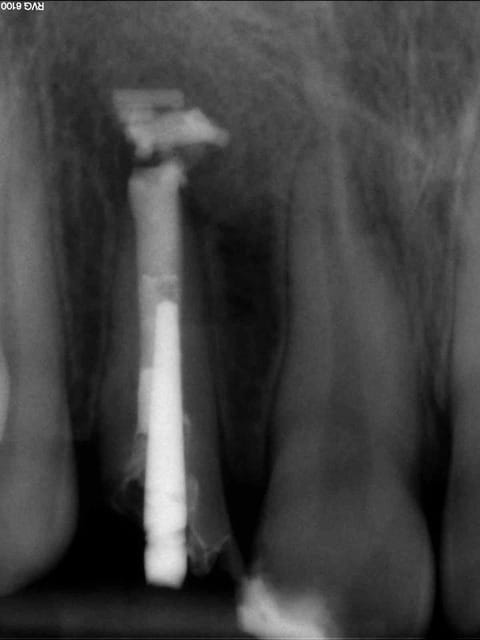

Cas clinique loin d'être parfait et je n'en était pas très fier :

12 ans

Traitement réalisé au MTA, j'ai merdé dans le placement du MTA comme on peut le voir sur la radio...

Radio 1 an post op : cicatrisation osseuse, plus de symptômes et pas d'inflammation particulière autour du MTA. Les parents sont prévenus que si ça pose problème on y retourne en chir.

PS : Ce n'est pas moi qui gère la prothèse, les parents n'ont pas donné suite au traitement coronaire proposé par leur dentiste... dommage